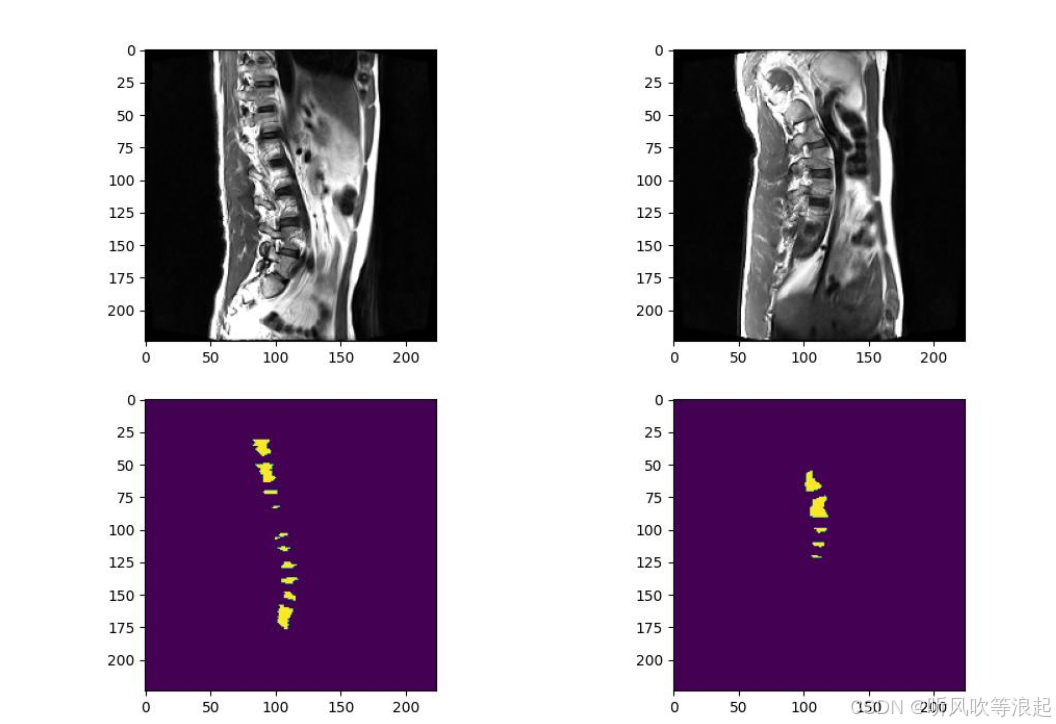

5.脊椎分割实验

这里仅仅训练了5个epoch用于测试代码的可行性,指标不做参考

因为unet的结果很好,这里只展示unet,而非deeplabv3

预处理数据可视化结果---->trainSetVis.jpg